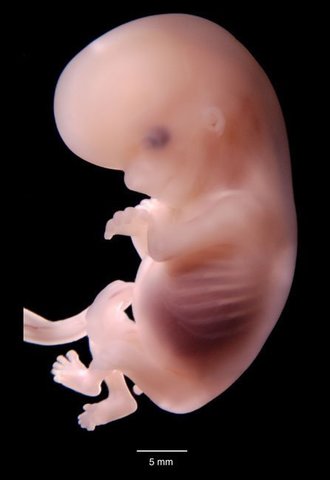

• 8 semanas. Características externas

8 semanas. Características externas

-La cabeza es casi la mitad de la longitud del feto

-La flexión cervical en de cerca de 30 grados

-Están presentes genitales externos indiferenciados

-Los ojos son convergentes

-Los párpados están fusionados

-Desaparece la cola

-Las narinas están ocluidas por unos tapones epiteliales

• 8 semanas. Características internas

8 semanas. Características internas

-Se produce la herniación del intestino medio hacia el cordón umbilcal

-La porción extraembrionaria de la alantoides ha degenerado

-Se forman los conductos y los alveólos de las glandulas lacrimales

-Los conductos paramesonéfricos comienzan a regresar en los varones

-Se produce la recanalización de la luz del tubo intestinal

-Los pulmones comienzan a tomar apariencia glandular

-El diafragma está completo

-Comienza la primera osificación en el esqueleto

-Sistema definitivo del arco aórtico